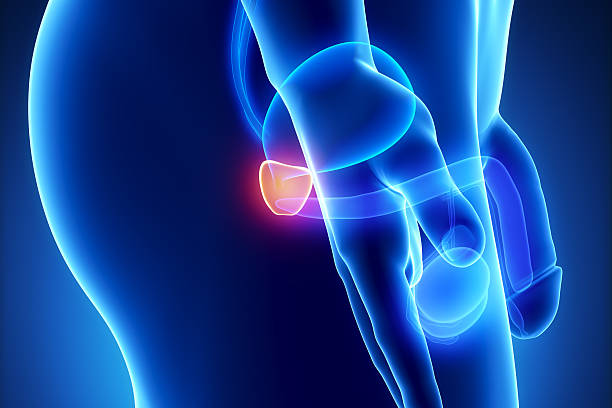

전립선암은 초기에는 증상이 거의 나타나지 않아 발견이 어렵습니다. 하지만 조기에 검진하여 발견된 전립선암의 경우 치료 가능성이 높아집니다. 따라서 전립선암 초기 증상을 알아두고, 정기적인 검진을 받아야 합니다. 이는 특히 합병증 예방을 위해 보다 중요한데 립선암은 진행되면서 합병증을 일으킬 가능성이 있습니다. 예를 들어, 골다공증, 방광 기능 장애, 성기능 장애 등이 그 예입니다. 따라서 초기에 전립선암을 발견하여 합병증 예방을 위한 조치를 취할 필요가 있어 이번 시간에는 전립선암 초기증상에 대해 자세히 알아보겠습니다.

전립선은 방광 주위에 위치하여 방광의 출구를 둘러싸고 있습니다. 전립선암이 발생하면 종양이 전립선을 압박하여 방광의 기능을 저해할 수 있습니다. 이로 인해 방광이 완전히 비어지지 않고 남아있을 수 있어 소변을 제대로 제어하기 어려울 수 있습니다. 이로 인해 요실금이나 배뇨 중 통증을 경험할 수 있습니다.

전립선암이 발생하면 전립선이 방광 출구를 압박하거나 방광 근육을 자극하여 배뇨를 어렵게 할 수 있습니다. 이로 인해 소변이 완전히 배뇨되지 않고 방광에 남아있을 수 있어, 소변을 보내기 어려워질 수 있습니다.